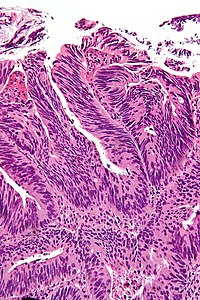

A positive surgical margin (ink on tumour) in urothelial carcinoma. H&E stain.